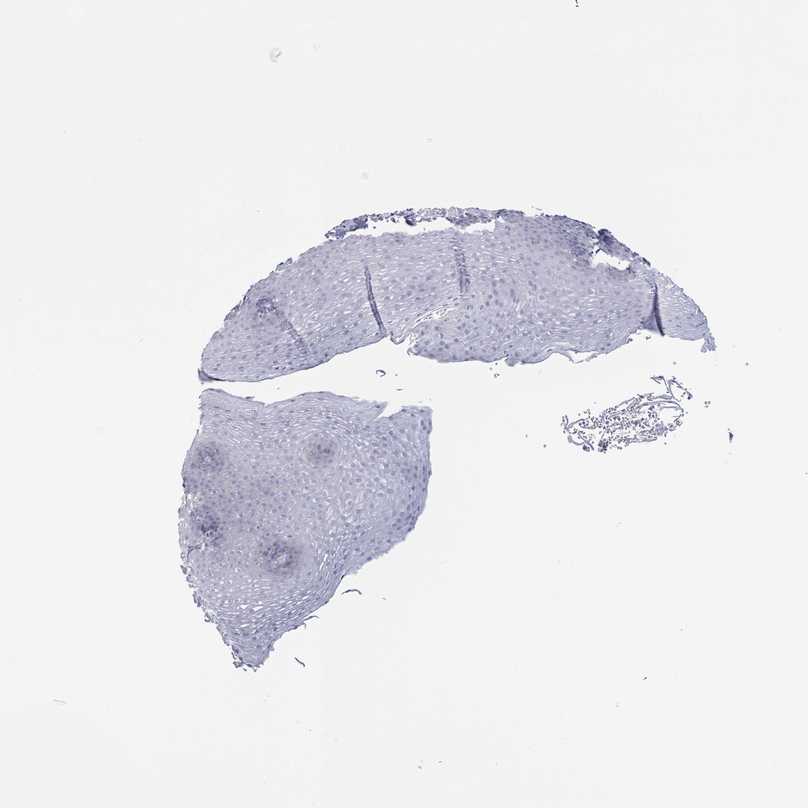

ESOPHAGUS - Antibody stainingi

Antibody staining in the annotated cell types in the current human tissue is reported as not detected, low, medium, or high, based on conventional immunohistochemistry profiling in selected tissues. This score is based on the combination of the staining intensity and fraction of stained cells.

Each image is clickable and will lead to virtual microscopy that enables deeper exploration of all samples and also displays staining intensity scores, fraction scores and subcellular localization as well as patient and tissue information for each sample.

Antibody HPA051839

Squamous epithelial cells Not detected